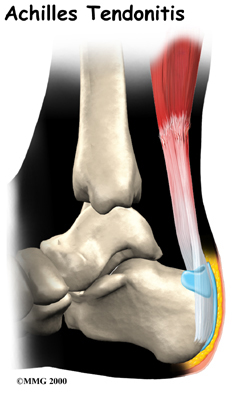

Achilles Tendonitis

Achilles tendonitis is a common issue that develops when the large tendon that extends down the back of the lower leg becomes inflamed. The Achilles tendon connects the calf muscle to the heel bone, and it is the largest tendon in the body. This tendon facilitates standing, walking, running, and climbing.

The robust structure of the Achilles tendon can generally withstand the stress of strenuous movements such as jumping or running, but it is also prone to inflammation due to overuse. Achilles tendonitis also increases the risk of an Achilles rupture, in which the tendon detaches from the heel bone or tears completely in half. Continuing to bear weight upon an inflamed tendon increases susceptibility to a more serious injury (e.g., rupture).

There are two types of Achilles tendonitis: insertional Achilles tendonitis and non-insertional Achilles tendonitis.

Insertional Achilles tendonitis refers to damage of the lower part of the tendon where it inserts (attaches) to the heel bone. This form of tendonitis is common in runners. Non-insertional Achilles tendonitis occurs when collagen fibers in the middle of the tendon begin to develop microscopic tears, usually due to wear and tear. Younger active individuals (athletes) tend to experience this type of tendonitis.